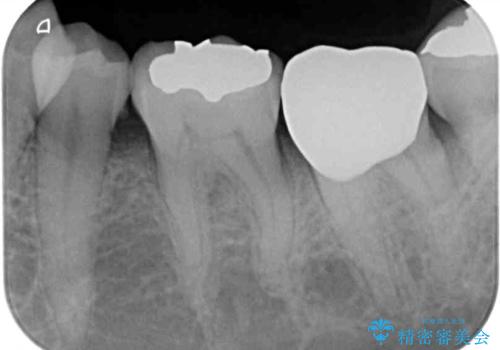

- 銀歯やインレーが外れたまま放置された奥歯の治療を希望して来院された患者様です。

咬合力が著しく強いため、欠損の多い歯はフルジルコニアクラウンへ、その他の虫歯はゴールドインレー(PGAインレー)にて修復することとしました。

来院時は全てセラミックでの治療を希望されていましたが、歯列や咬み合わせから咬合力による破損リスクが高いと判断されたため、ゴールドインレーを選択しました。